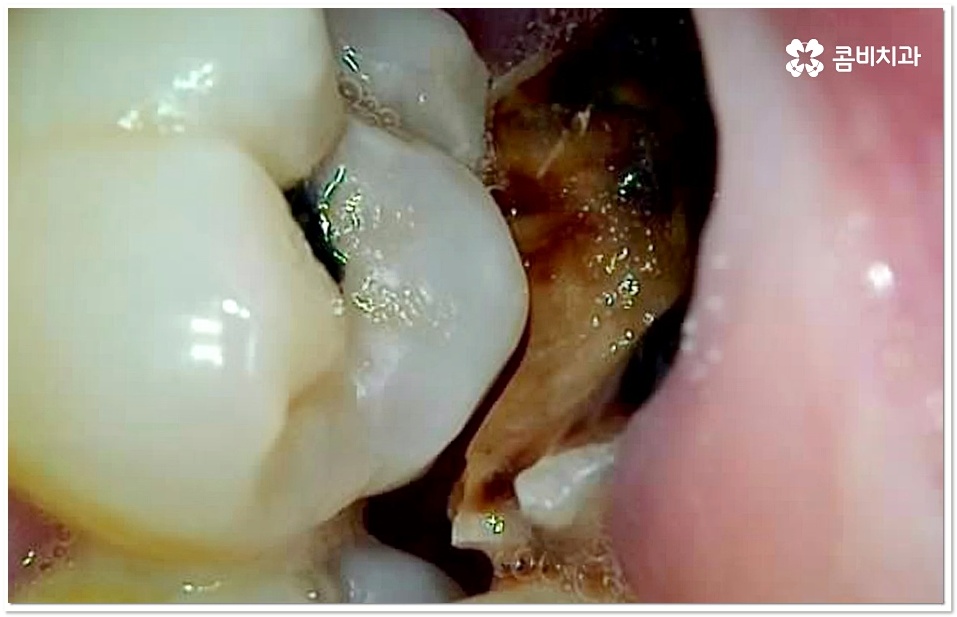

특히 20살 전후로는 사랑니 때문에 인접면 충치가 자주 발생할 수 있으니 신경써 주시길 권유드리고 있는데요. 어금니 뒤쪽으로 사랑니가 나올 때 비정상적으로 맹출이 되어 비스듬한 각도로 어금니와의 사이에 좁은 틈새를 만들게 되면 음식물 찌꺼기가 잘 끼고 쉽게 빠지지 않아 더욱 충치나 잇몸 염증이 유발되기 쉬우니 신경써서 관리해 주시길 바라고 있어요.

이 단계도 지나 치수까지 세균이 침투하게 되면 신경이 변성되고 통증이 심해지기 때문에 신경치료를 통해 이를 제거하고 내부에 충전재를 채워 밀봉한 뒤 전체를 덮어씌우는 크라운 치료를 해 주는데, 이와 같은 보존적 어금니 충치치료 로 자연 치아를 발치하지 않고 내구성을 좀 더 늘릴 수 있습니다.